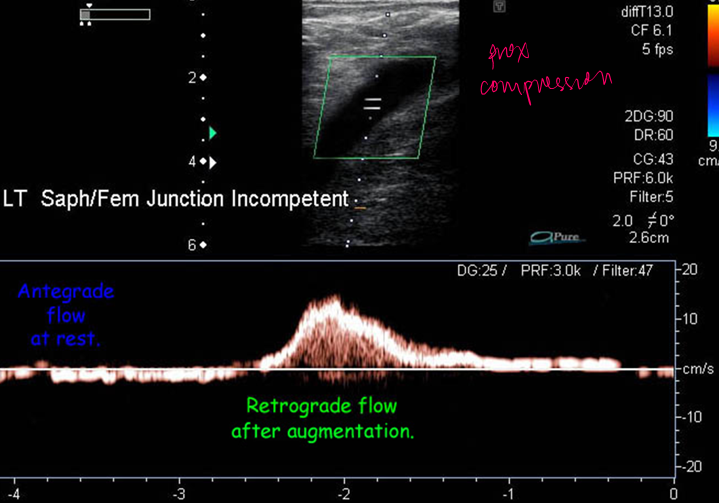

normal or abn

abn → incomp vein